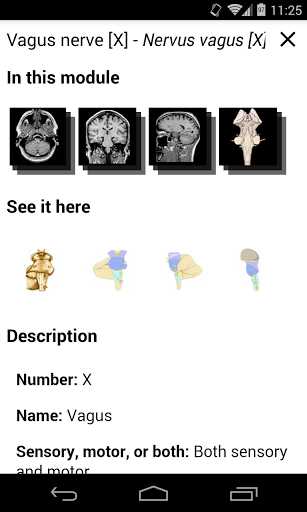

e-Anatomy memiliki lebih dari 26.000 gambar yang berisi serangkaian gambar dalam tampilan aksial, koronal, dan sagital serta radiografi, angiografi, gambar diseksi, bagan anatomi, dan ilustrasi. Semua gambar medis diberi label dengan cermat, lebih dari 967.000 label tersedia dalam 12 bahasa termasuk Terminologia Anatomica Latin.

- Ketuk label untuk menampilkan struktur anatomi